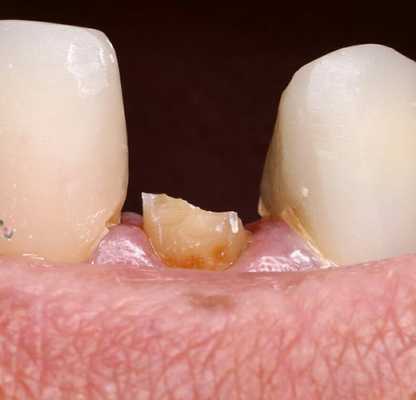

Пациентка М., 35 лет, обратилась в клинику с жалобами на расцементировку коронки из оксида алюминия на 2.1. Объективно: коронка имела подвижное положение на культе зуба 2.1 и без усилий извлеклась. Отмечался откол 1/3 культи зуба (внутренняя часть коронки была заполнена отделившимся фрагментом).

Дефект культи 2.1 зуба

Зуб в прошлом подвергался эндо лечению с последующим восстановлением с использование полимерного штифта. Отмечалось полное сохранение полимерного штифта на всем протяжении. Откололась только внутренняя поверхность коронки с фрагментом культевого материала.